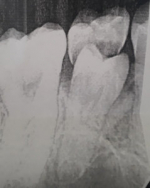

Коренной зуб растет перед молочным фото

Если коренной зуб растет перед молочным или позади него, врач решает, что предпринять в этой ситуации, только при личном осмотре. Для выбора правильной тактики лечения важен возраст ребенка, насколько прочно молочный зуб закреплен в десен и насколько сильно уже вырос коренной, нет ли у ребенка других стоматологических аномалий или заболеваний, которые могут быть источниками этой проблемы и пр.